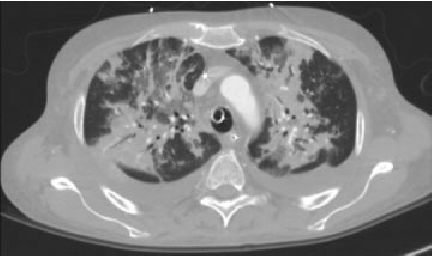

Kəskin mediastinitin diaqnozunu dəqiqləşdimək üçün ən vacib müayinə KT-dir. KT-də divararalığında ödem, maye, hava, kontrast ekstravazasiyası mediastinitin xarakterik əlamətləridir.

- KT-də divararalığında ödem, maye, hava, bəzən də kontrast ekstravazasiyası (Şəkil 10)

KT-də divararalığında ödem, maye, hava, kontrast ekstravazasiyası